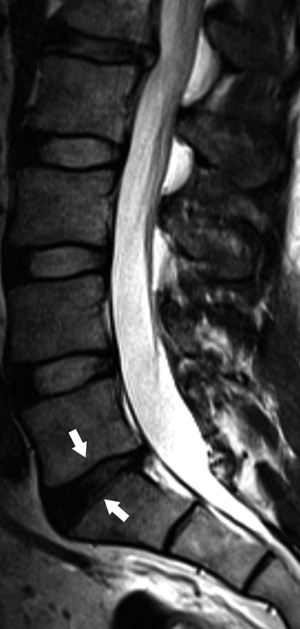

Prolapser som disloserer eller komprimerer nerverøtter er imidlertid sjeldent hos symptomfrie (15, 18) (fig 3). Finner man denne typen prolaps kombinert med symptomer som passer med den aktuelle nerverot, vil man ha etablert en sannsynlig årsakssammenheng. Prolapser er ikke stabile strukturer. Særlig de som har en smal basis mot skiven viser stor tendens til resorpsjon. Under konservativ behandling vil en tredel skrumpe i løpet av de første seks uker og to tredeler i løpet av seks måneder (13). Funn av skiveprolaps er altså i seg selv ikke indikasjon for kirurgisk behandling. Som alltid er det kliniske bildet avgjørende.